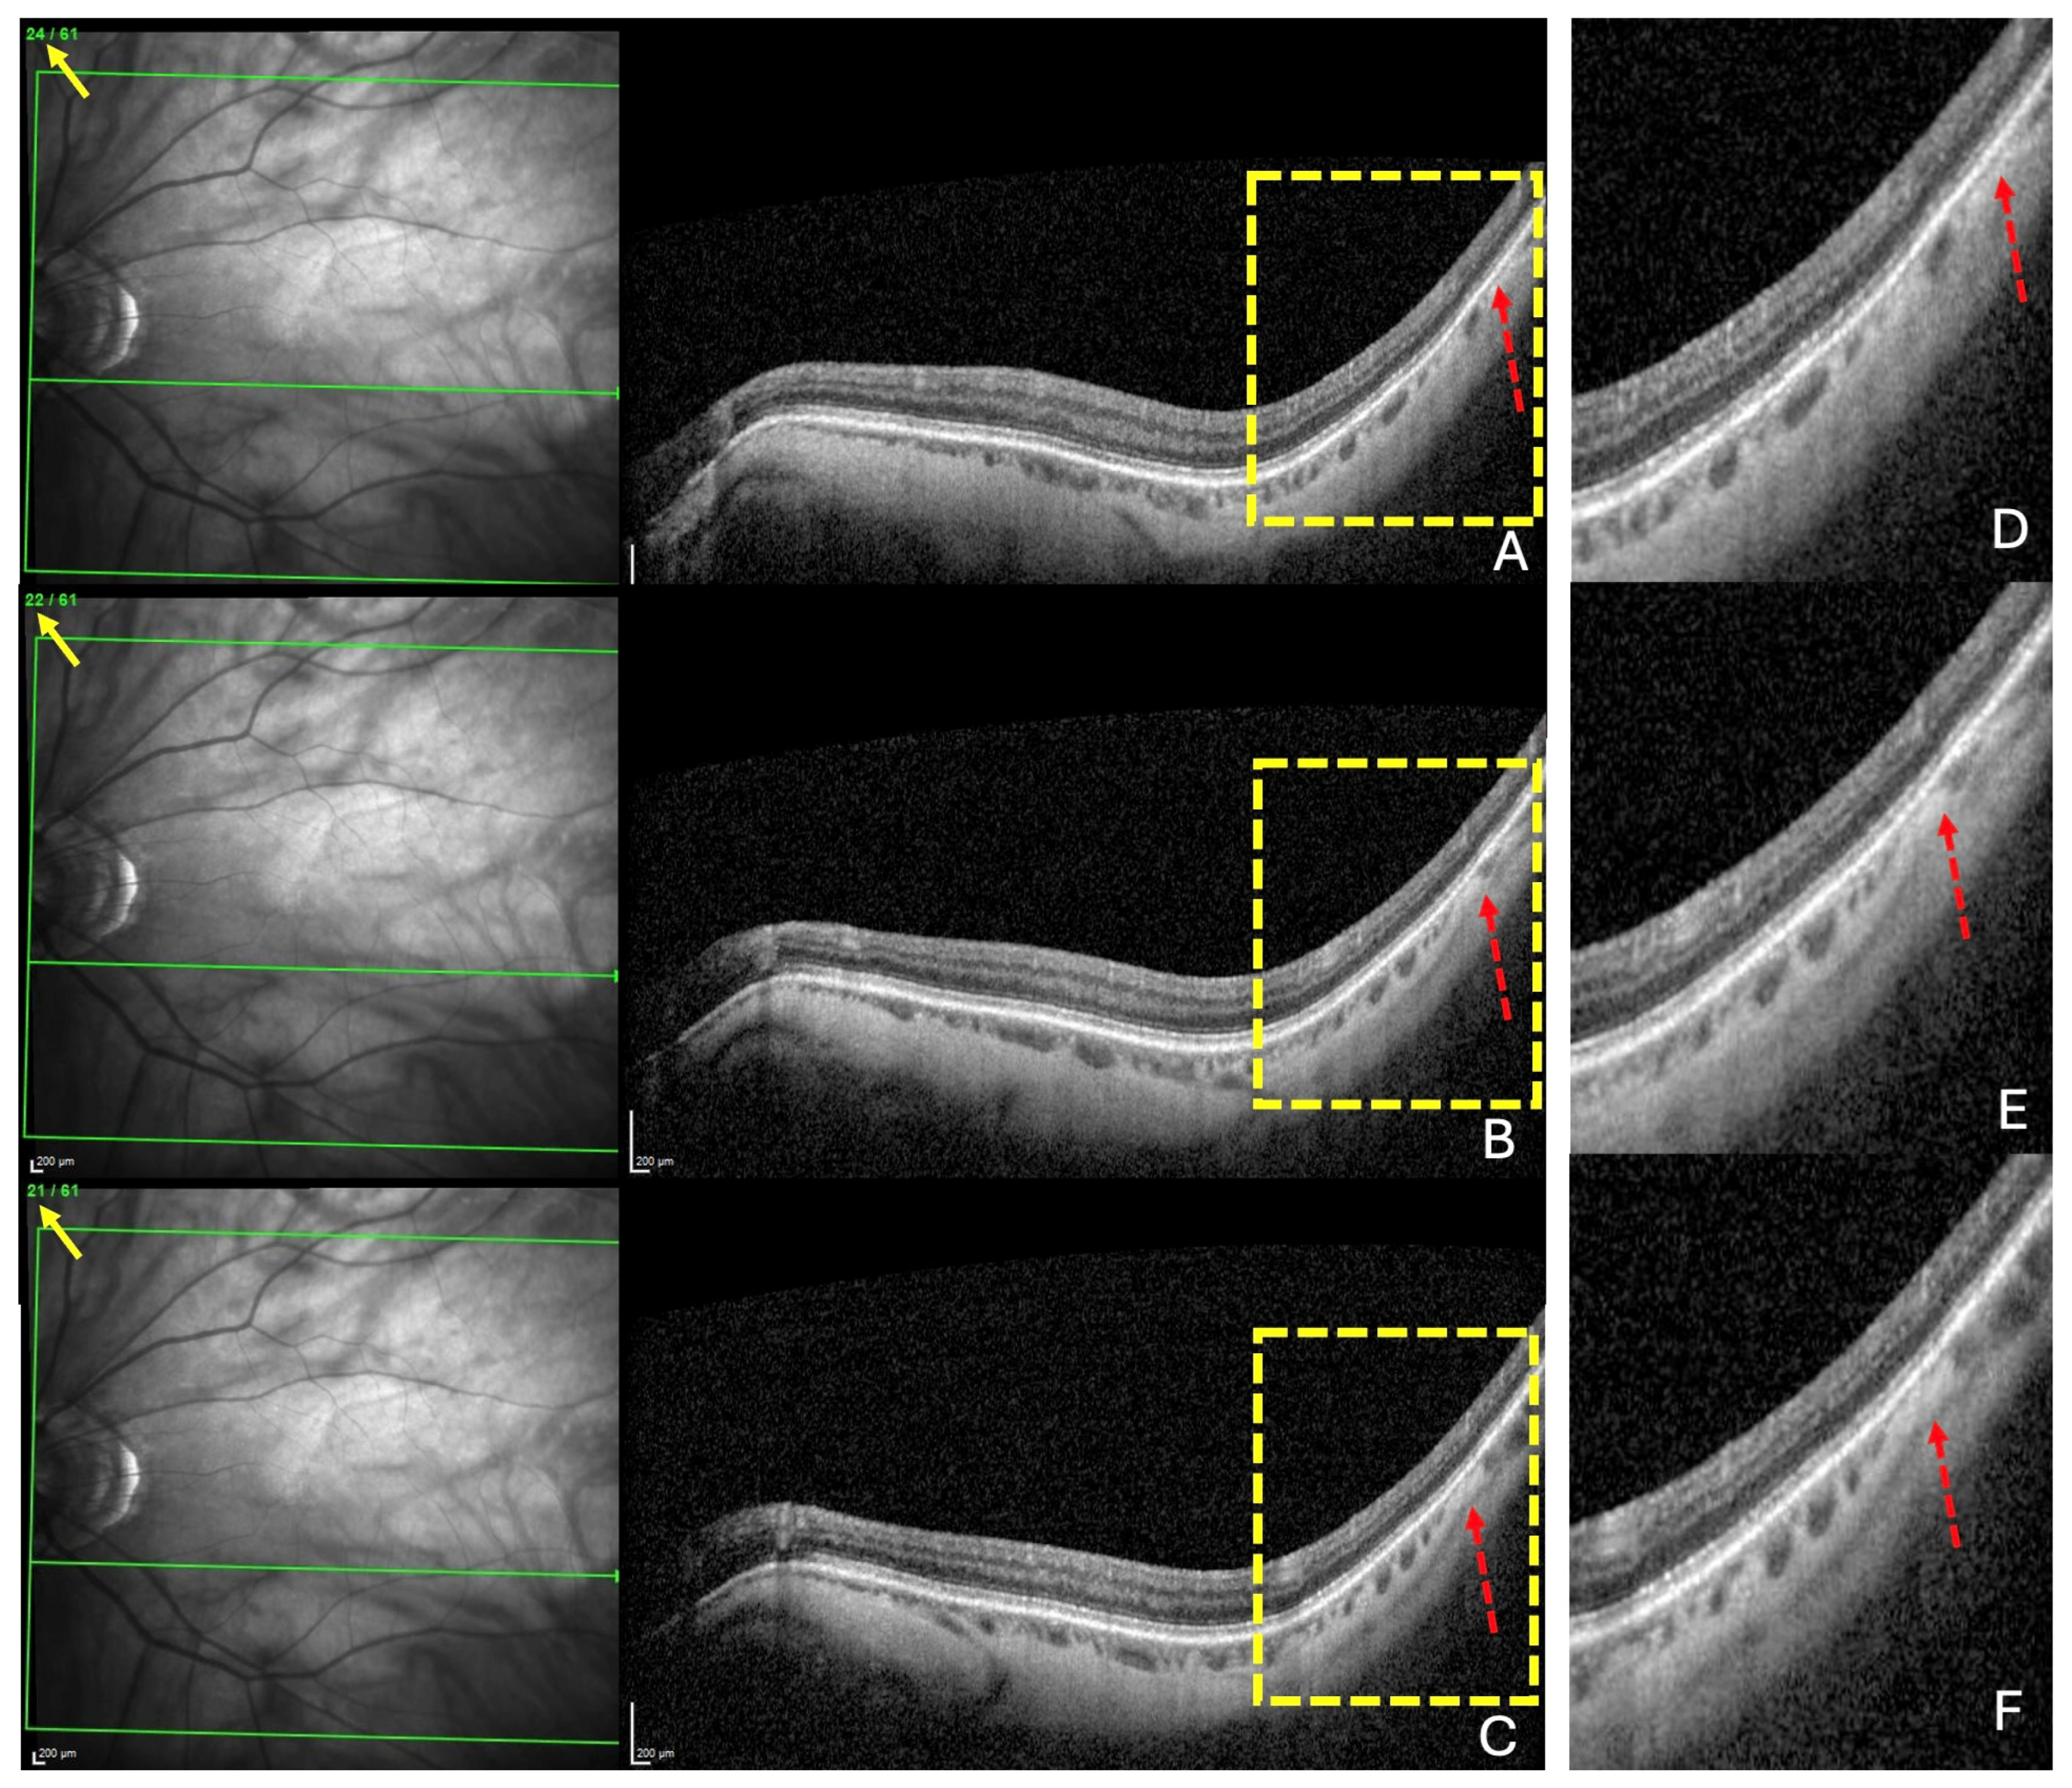

- A search for choroidal thinning in 3 locations in the temporal part of the posterior pole.

- Measurement of the choroidal thinning and distance from fovea to thinning.

3.4. Detailed Analysis of Choroidal Thinning at the Vicinity of the Fo-BMO Axis (ChT)